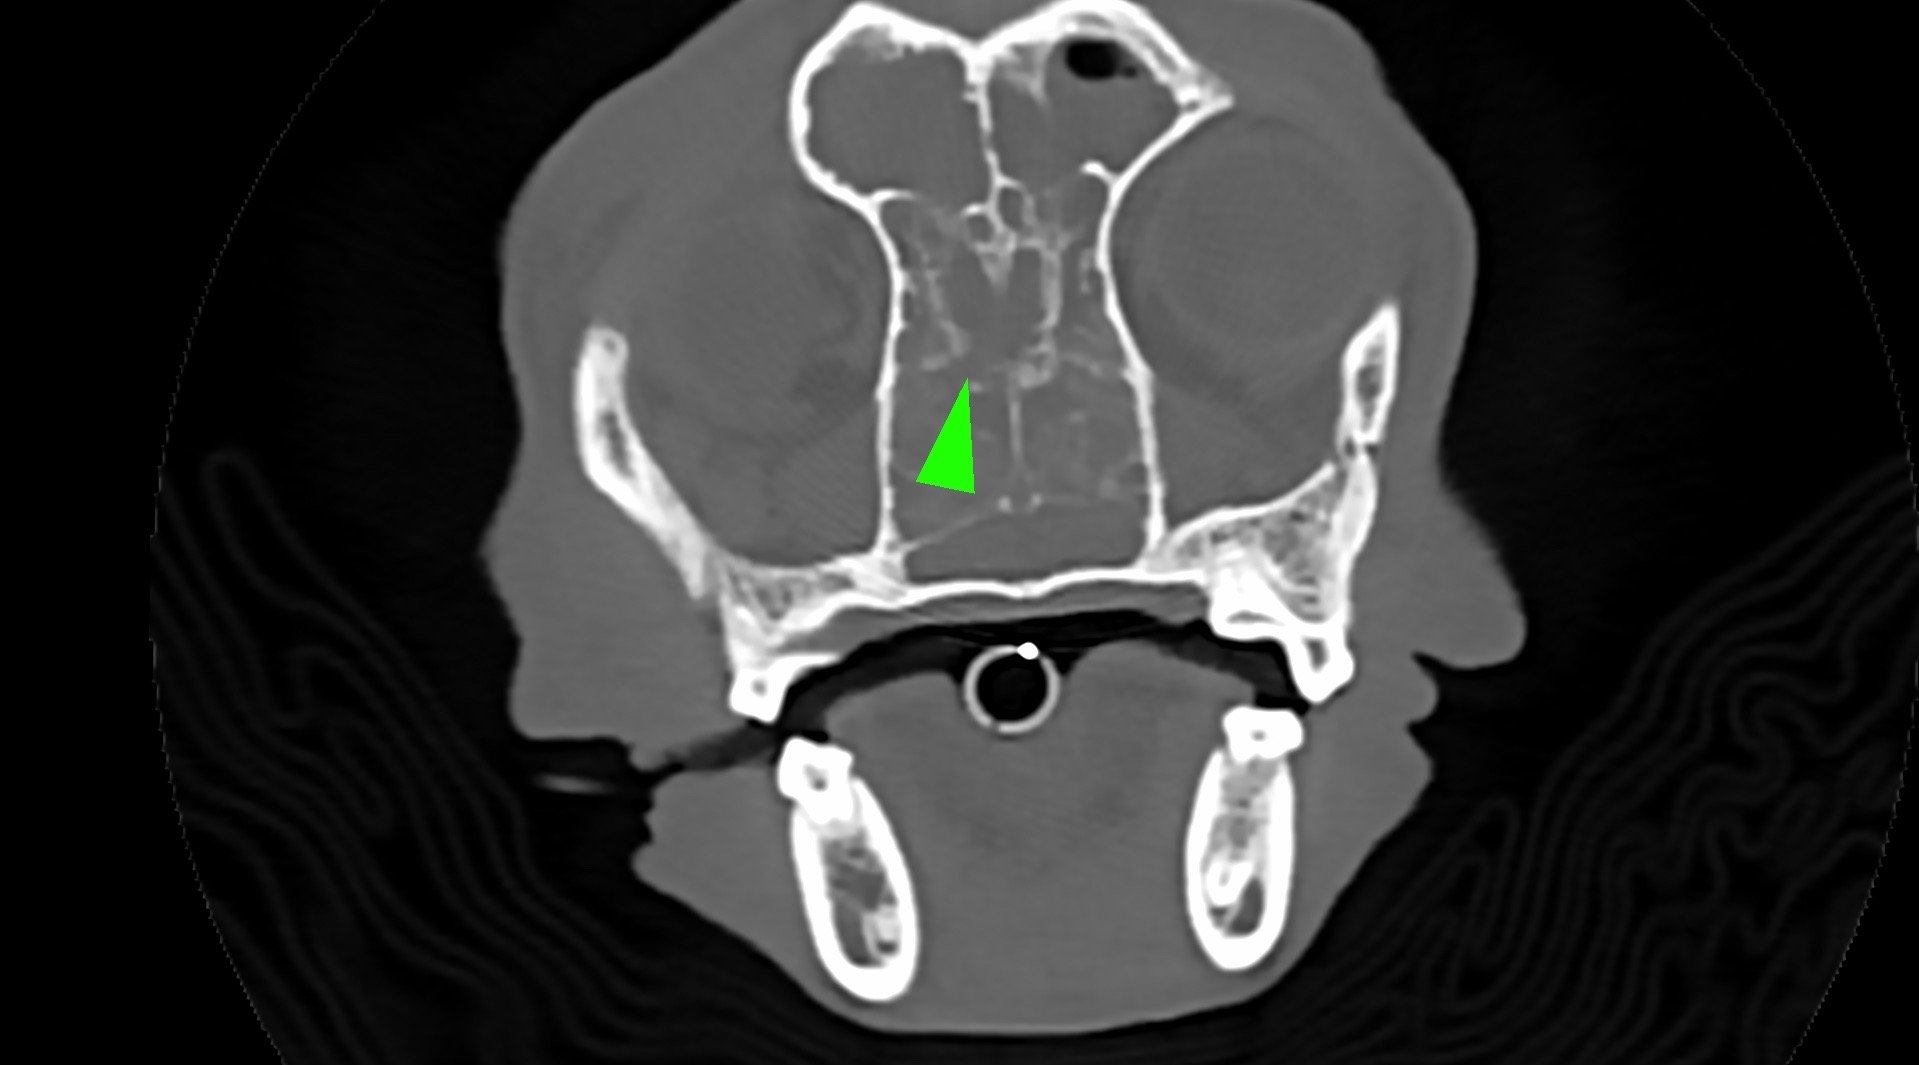

柴犬皮皮因長期有鼻塞、流鼻血、流鼻水的症狀來築心就診,在這之前已經換過兩間醫院,但治療效果都不太好。在一系列的評估後,我們為皮皮安排了電腦斷層以及鼻腔內視鏡的檢查,檢查後發現在皮皮的鼻腔內有疑似腫瘤的團塊,並且向後侵入鼻竇,甚至已經接近大腦。我們運用內視鏡設備採樣取得了團塊的切片,並得到鼻上皮細胞癌的診斷。